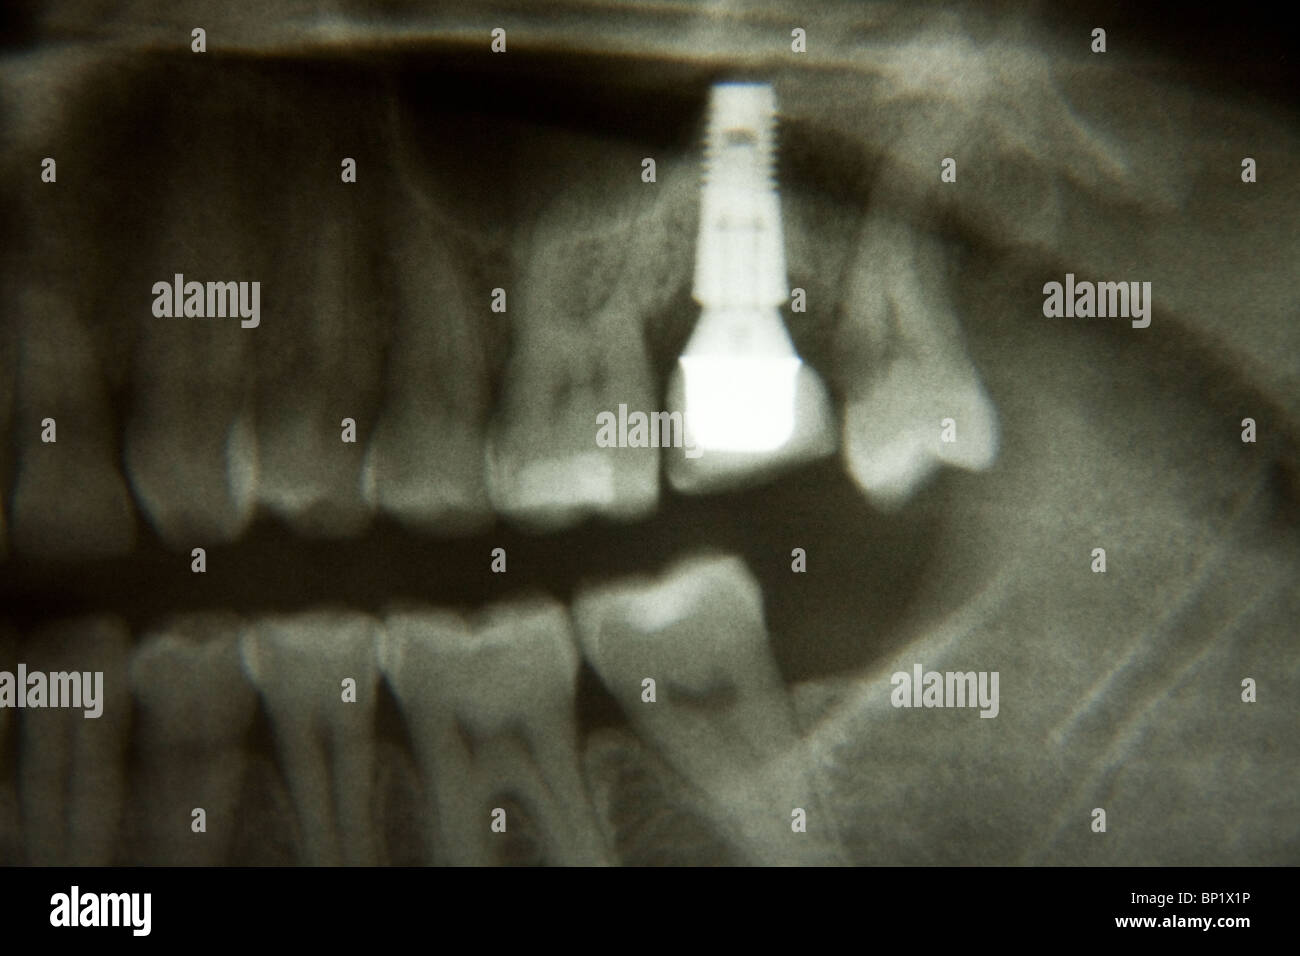

Dental implant, Xray Stock Image C026/9870 Science Photo Library X Ray Dental Implant Quantity) of bone is key for. radiographic imaging in implant dentistry. Amir azarpazhooh and jim yuan lai. radiographic imaging is key in all phases of dental implant therapy, i.e., diagnosis, planning and assessment of treatment,. Quality) and alveolar height and width (i.e. When used in oral implantology, this. Discussion of this chapter is specifically focused on radiographic imaging. X Ray Dental Implant.